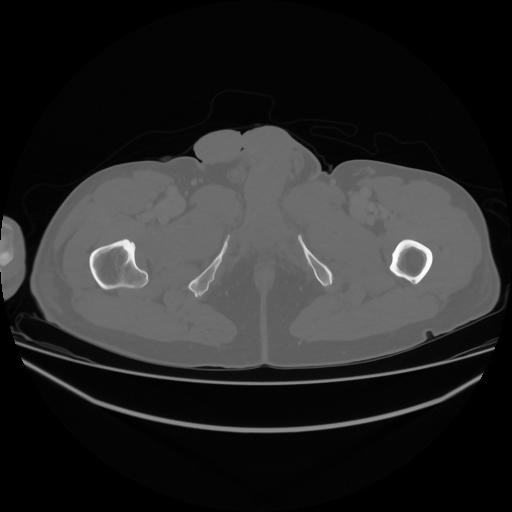

5 CUERPO,CE,Vol,1.0,CUERPO,,